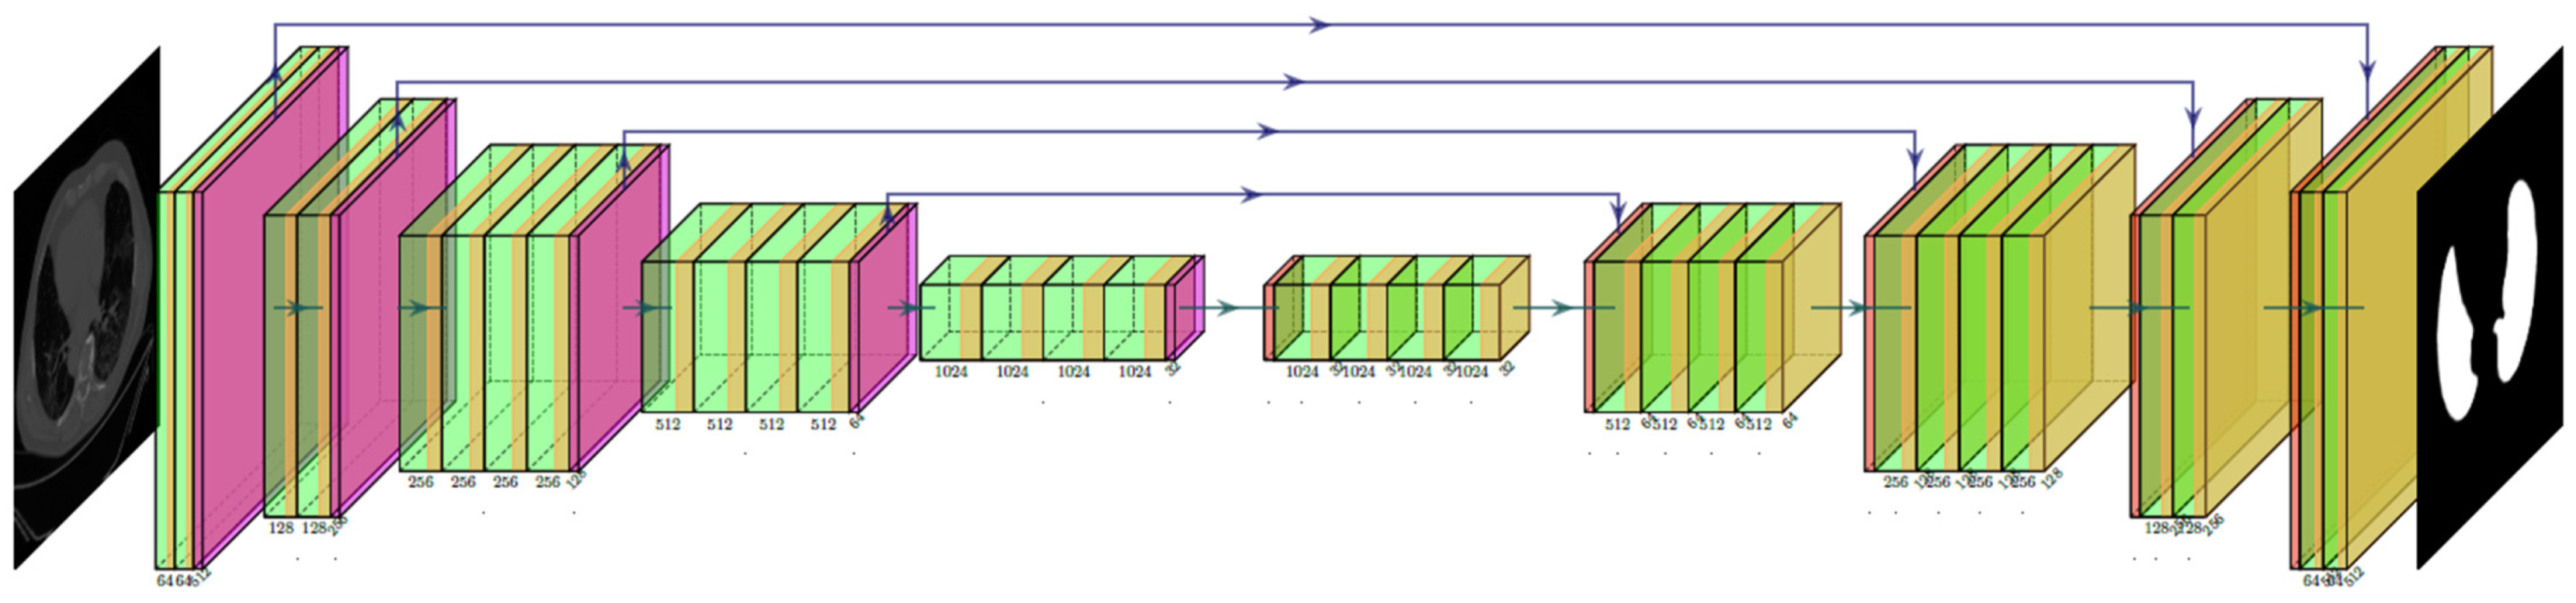

2.2. Architecture

2.2.1. Three AI Models: PSP Net, VGG-SegNet, and ResNet-SegNet

2.2.2. Loss Functions for AI Models